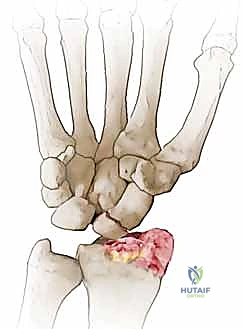

متلازمة SNAC (Scaphoid Nonunion Advanced Collapse) هي حالة تدهور تدريجي ومأساوي لمفصل الرسغ. تبدأ القصة بكسر في العظم الزورقي (غالباً بسبب السقوط على يد ممدودة). إذا لم يتم تشخيص هذا الكسر أو لم يلتئم بشكل صحيح، فإن العظم الزورقي ينقسم إلى قطعتين تتحركان بشكل غير طبيعي ومستقل عن بعضهما البعض.

هذه الحركة غير الطبيعية تخلق احتكاكاً مستمراً (Micro-trauma) مع العظام المجاورة، وتحديداً عظم الكعبرة (Radius). بمرور الوقت (أشهر أو سنوات)، يؤدي هذا الاحتكاك إلى تآكل الغضاريف الناعمة التي تغطي العظام، مما يسبب خشونة مفصلية شديدة (Osteoarthritis).

- المرحلة الأولى (Stage I): خشونة وتآكل في المفصل بين القطب البعيد للعظم الزورقي وعظم الكعبرة (الناتئ الإبري الكعبري).

تُعد عملية استئصال القطب البعيد للعظم الزورقي (Excision of the Distal Pole of the Scaphoid) حلاً جراحياً ذكياً ومبتكراً. الفكرة الميكانيكية وراء هذه الجراحة هي: "إذا كان القطب البعيد للعظم الزورقي هو الذي يحتك بعظم الكعبرة ويسبب الألم والخشونة، فلنقم بإزالته مع الحفاظ على باقي هياكل الرسغ".

- الاستئصال الدقيق: باستخدام أدوات جراحية ميكروسكوبية دقيقة، يتم استئصال حوالي 3 إلى 4 مليمترات من القطب البعيد للعظم الزورقي. هذه الكمية كافية لمنع الاحتكاك مع عظم الكعبرة، وفي نفس الوقت تحافظ على استقرار الأربطة.